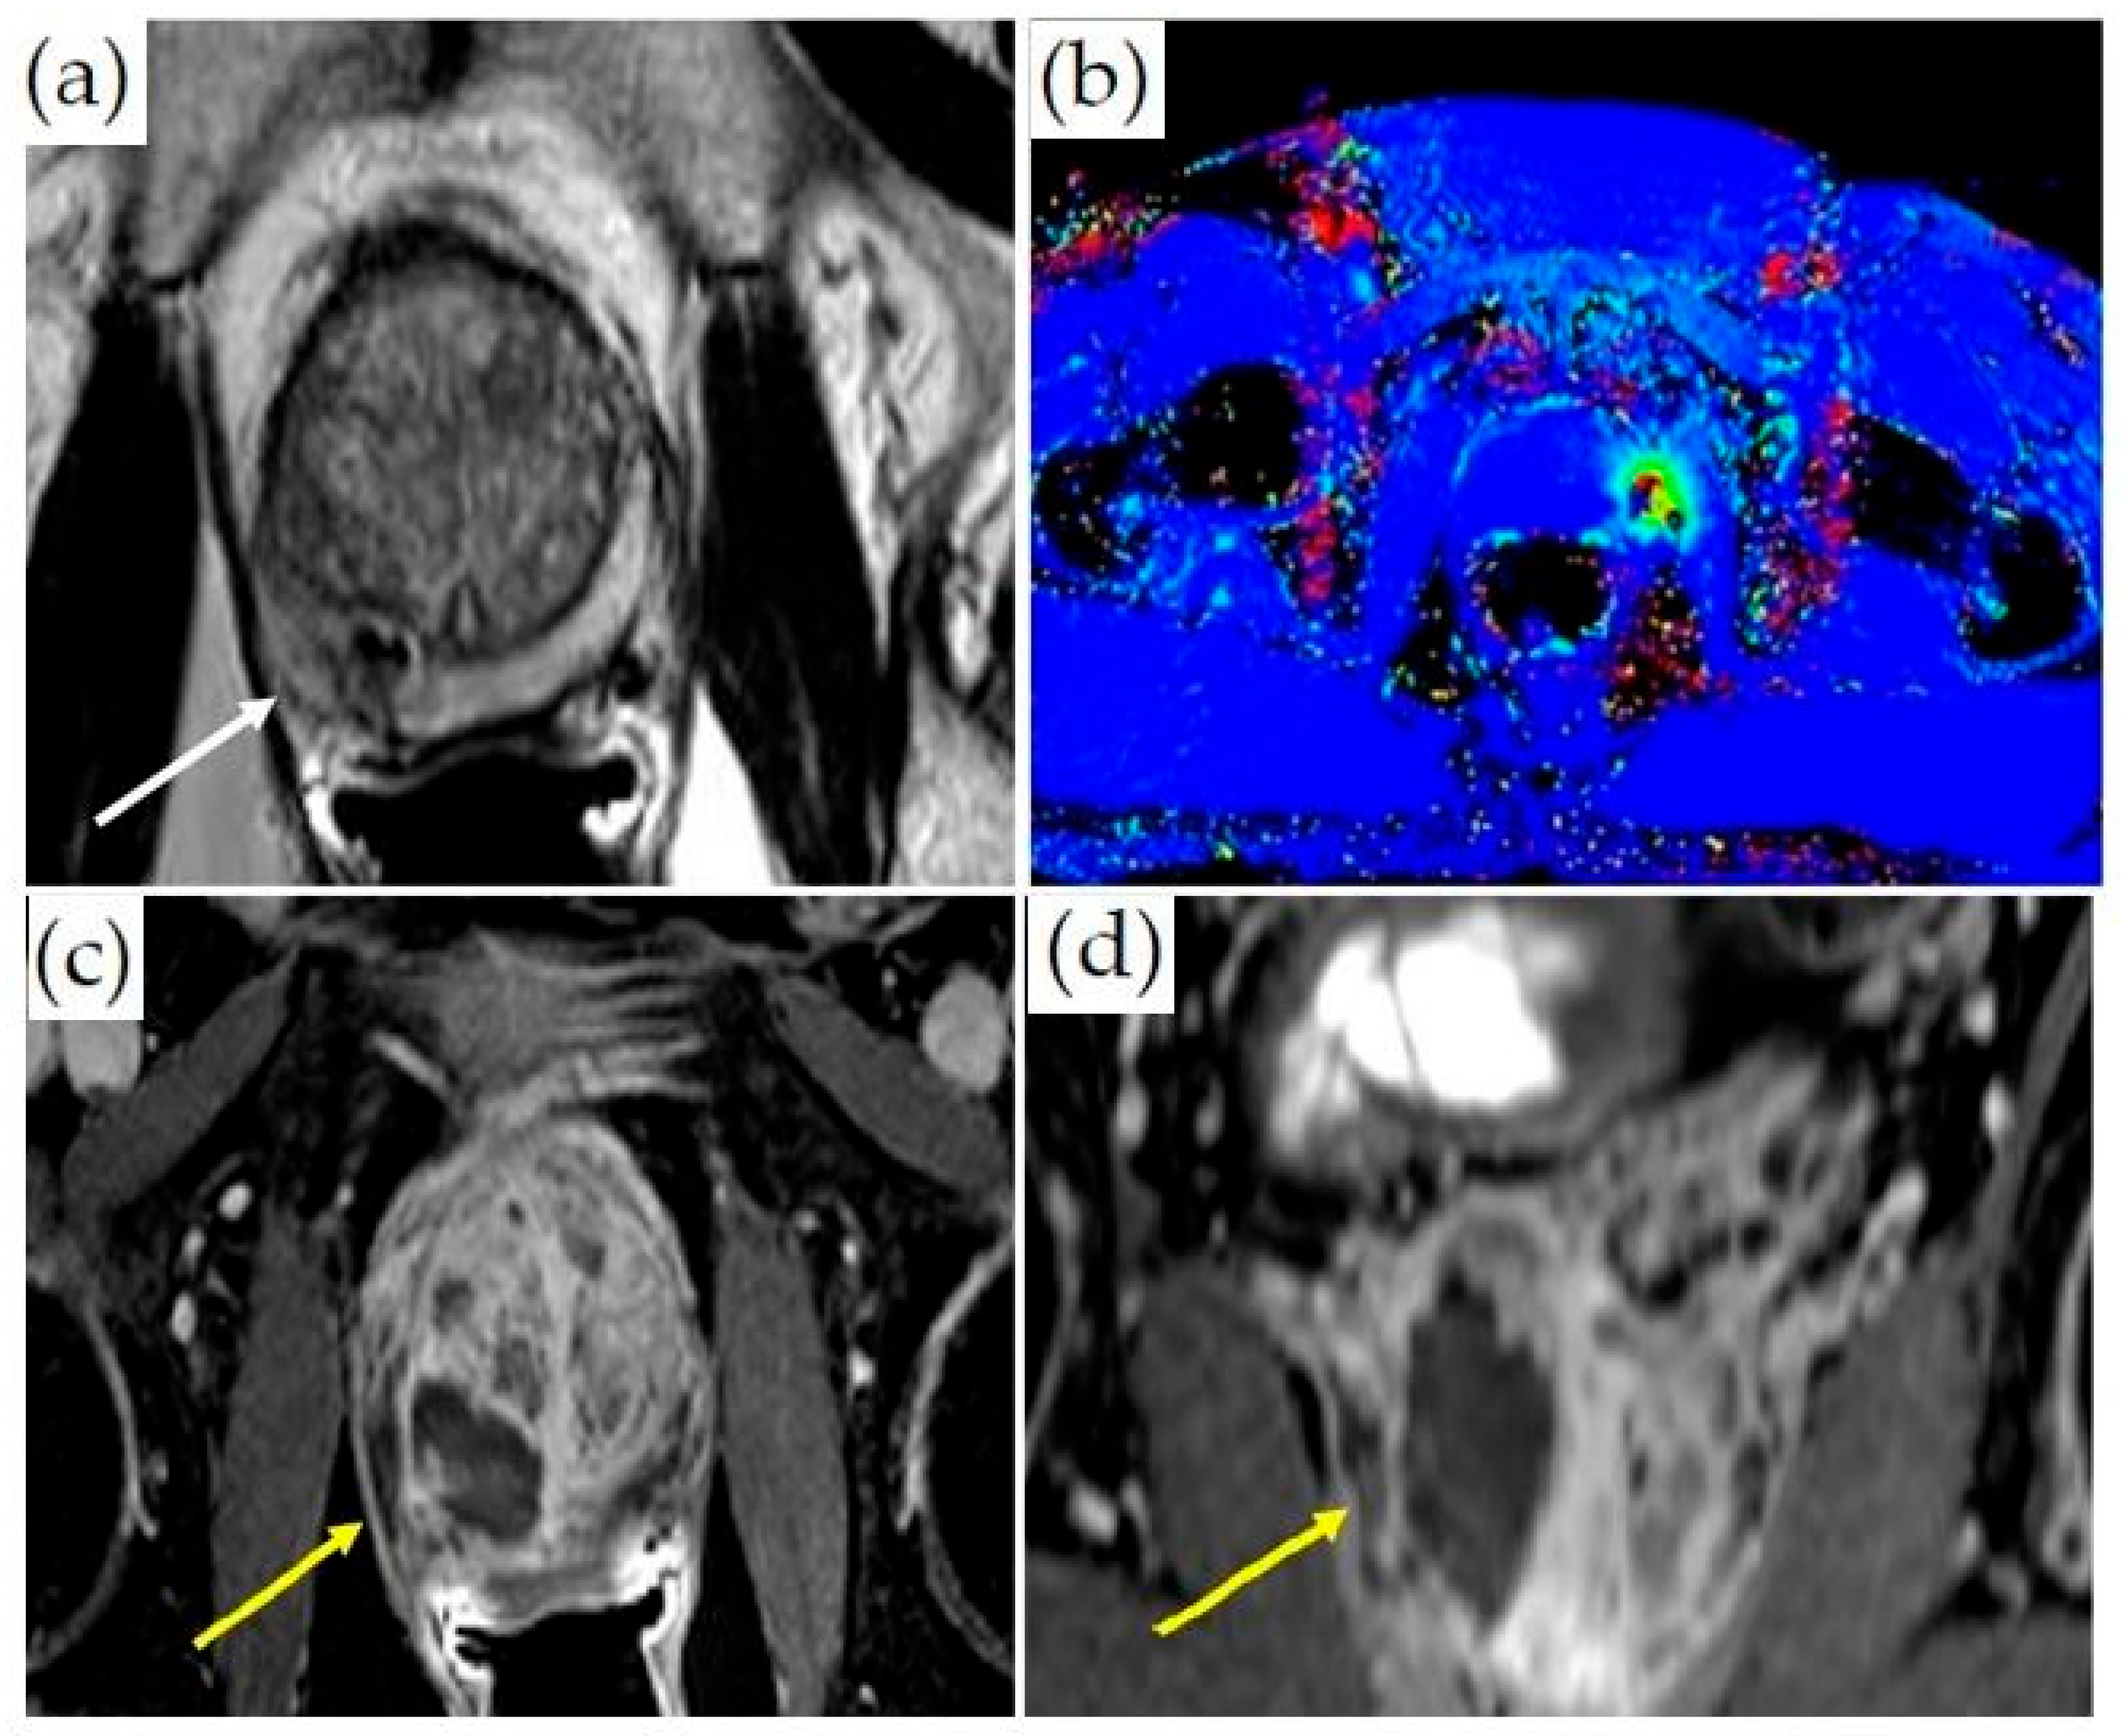

3.3. MRI-Guided Cryoablation